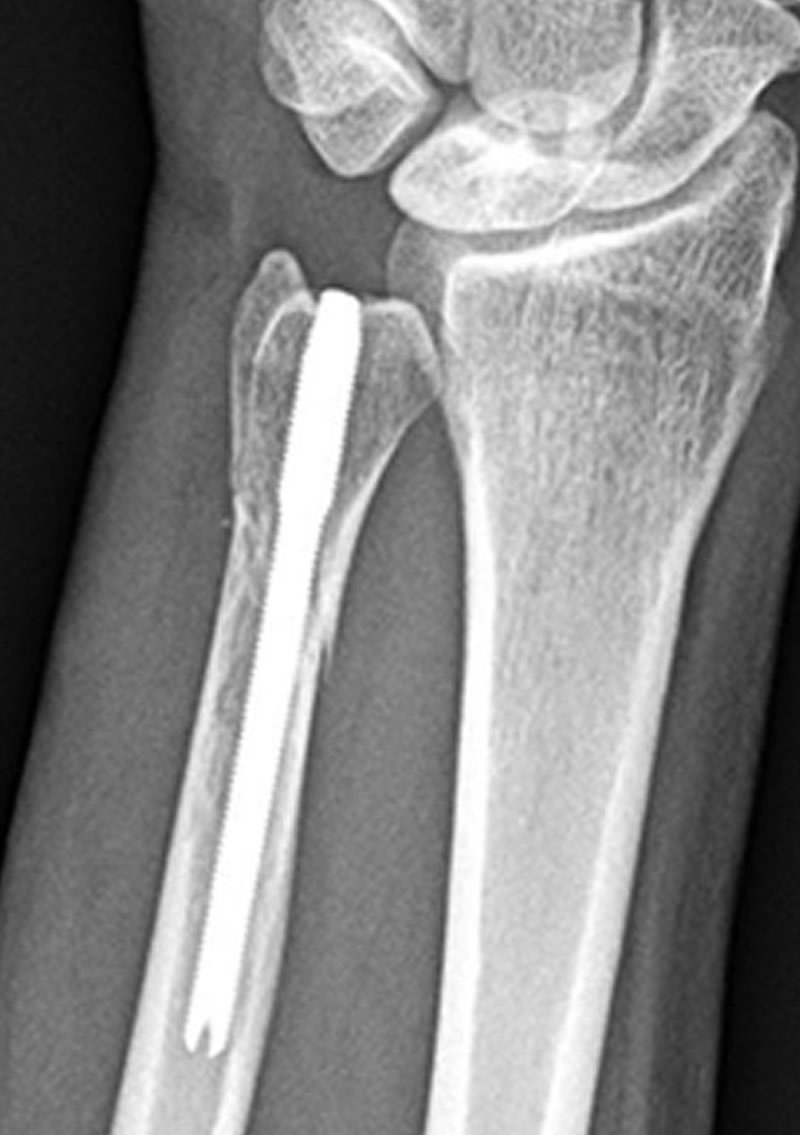

Distal Radius